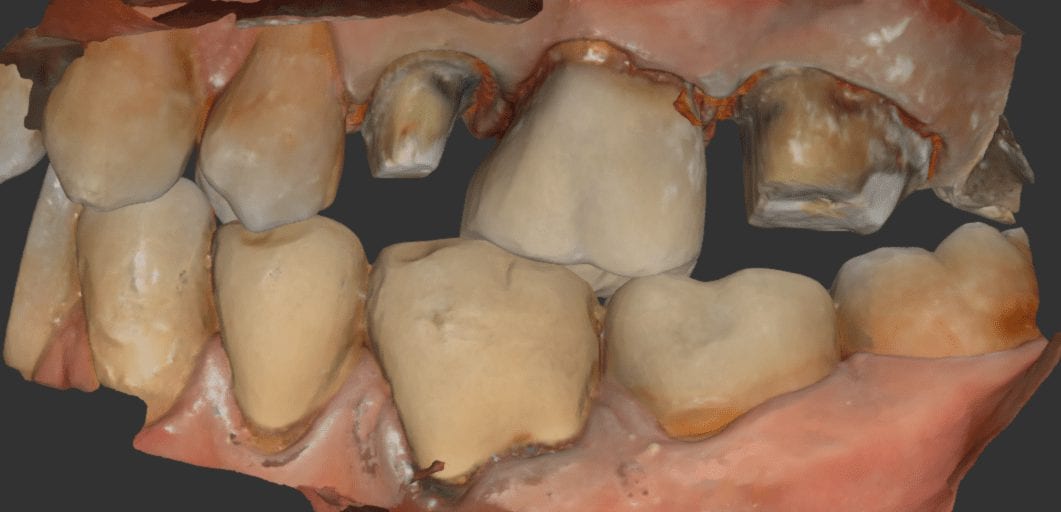

One of the greatest advantages of digital impressions is the ability to copy a pre-existing condition. This has a lot of benefits, one of which is that the patient will […]